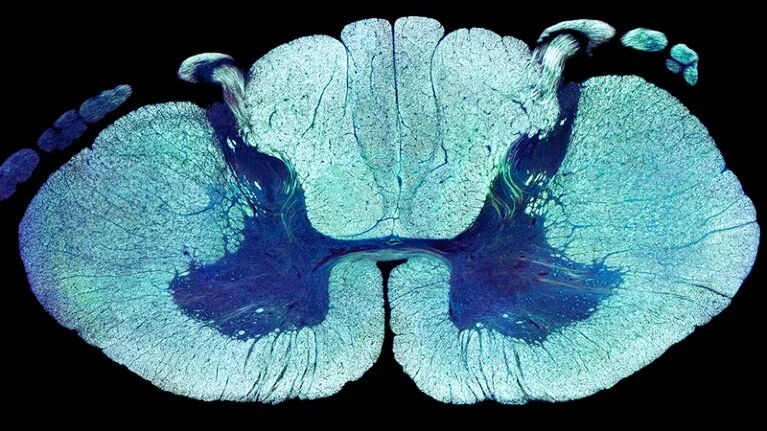

神经科学家鉴定出了帮助瘫痪人士重新行走的神经细胞,打开了靶向治疗的可能性,有望造福更多的脊髓损伤患者[1]。 重度脊髓损伤会破坏大脑与下脊柱神经细胞网络的连接,这一连接控制着我们的行走能力。2018年,洛桑联邦理工学院的神经科学家Grégoire Courtine和他的同事用研究表明,向下脊柱神经释放电脉冲——一项名为“硬膜外电刺激”(EES)的技术——同时结合高强度训练,或能让这类脊髓损伤患者重新行走[2]。一项临床试验的三名受试者都从重度或完全运动麻痹以及腿部只有极少知觉的状态,改善到能自主行走或借助步行器或拐杖迈步。其他两个团队也在2018年报道了类似结果[3,4]。 重塑特定神经元能让脊髓损伤得到部分恢复。来源:Steve Gschmeissner/SPL 如今,Courtine的团队进一步拓展了这项工作。他们证明了该系统也适用于腿部知觉完全丧失的患者。研究团队在《自然》发文称,同一项试验中的9名受试者——其中3人为全瘫,腿部毫无知觉——通过脊柱植入装置进行EES治疗并结合训练,重新恢复了行走能力。试验开始的5个月后,所有受试者都能承受自身体重并行走,同时借助步行器保持平稳。 4个人不再需要启动EES才能行走。这一持续恢复的迹象表明,电刺激激活了脊髓神经元的重塑,把人体运动网络重新调动了起来。 专门研究脊髓损伤的澳大利亚昆士兰大学神经学家Marc Ruitenberg说:“这为脊髓损伤患者带来了巨大的希望。” 活性受抑 Courtine的团队还发现了能增强康复效果的神经元。与直觉相反的是,如果启动人体内的EES,刺激位点的神经细胞活动反而会减少。研究团队利用该线索开展了一次从头到尾的研究。首先,研究团队用小鼠模拟了整个治疗过程——从受伤到电刺激再到利用辅助稳定性的机器人进行训练。最终结果与人体试验的结果相似。 接下来,团队测量了小鼠脊髓组织样本中数千个个体神经元的基因活性,并在此基础上绘制了下脊髓神经细胞类型的超详细图谱。他们随后再用一个机器学习算法寻找在EES辅助康复准备阶段出现基因活性变化的小鼠神经元,且这些变化需要与人类受试者行走能力中观察到的改变一致。 该算法发现有一个兴奋性中间神经元亚群似乎符合条件,兴奋性中间神经元是连接运动神经元和感觉神经元的神经细胞。当Courtine的团队使受伤小鼠的这些细胞沉默时,他们发现EES便不再能帮助受伤小鼠行走。 Courtine认为,康复期间该位点神经活性的整体下降反应了学习的过程。“仔细想想的话,这没什么奇怪的,”他说,“因为对大脑来说,这恰恰是学习任务时会有的表现——当你学上手了之后,激活的神经元也会越来越少。” 未来工作 目前没有哪种技术能从人体中收集这类直接证据。但加州索尔克生物研究所的神经学家Eiman Azim认为,可能是同一批神经元导致了这种效应,因为不同脊椎动物的脊柱结构非常相似,包括人类和小鼠。 Azim说,对脊柱环路的详细理解最终或能让神经科学家在其他疗法中直接操纵特定神经元的活性,比如基因疗法。Ruitenberg说,干细胞疗法今后或能将脊髓损伤中受损的关键神经元群替换掉。 Courtine和同事还利用EES恢复了猴子的手臂运动和抓取能力[5]。华盛顿大学的一个团队对6名脊髓损伤患者开展了相同的实验,他们使用的是贴在颈部的非侵入式电极皮肤贴片[6]。 虽然看到脊髓损伤患者重新行走令人惊叹,但Ruitenberg表示行走有时并非这些人的最大需求。膀胱控制、排便控制和性功能丧失也会严重影响生活质量。他说:“大家很想知道这项技术是否也能改善这些方面的功能。” Courtine说,鉴定出负责这些功能的神经是他接下来的目标之一,因为现在已经有了详细的分子图谱。他还在荷兰创立了ONWARD公司,专门对该技术进行商业化。该公司将于2024年开始在美国招募70-80名受试者。 参考文献: 1. Kathe, C. et al. Nature https://doi.org/10.1038/s41586-022-05385-7 (2022). 2. Wagner, F. B. et al. Nature 563, 65–71 (2018). 3. Gill, M. L. et al. Nature Med. 24, 1677–1682 (2018). 4. Angeli, C. A. et al. N. Engl. J. Med. 379, 1244–1250 (2018). 5. Barra, B. et al. Nature Neurosci. 25, 924–934 (2022). 6. Inanici, F., Brighton, L. N., Samejima, S., Hofstetter, C. P. & Moritz, C. T. IEEE Trans. Neural Syst. Rehabil. Eng. 29, 310–319 (2021). 原文以Electrical stimulation helps paralysed people walk again — and now we know why为标题发表在2022年11月9日《自然》的新闻版块上